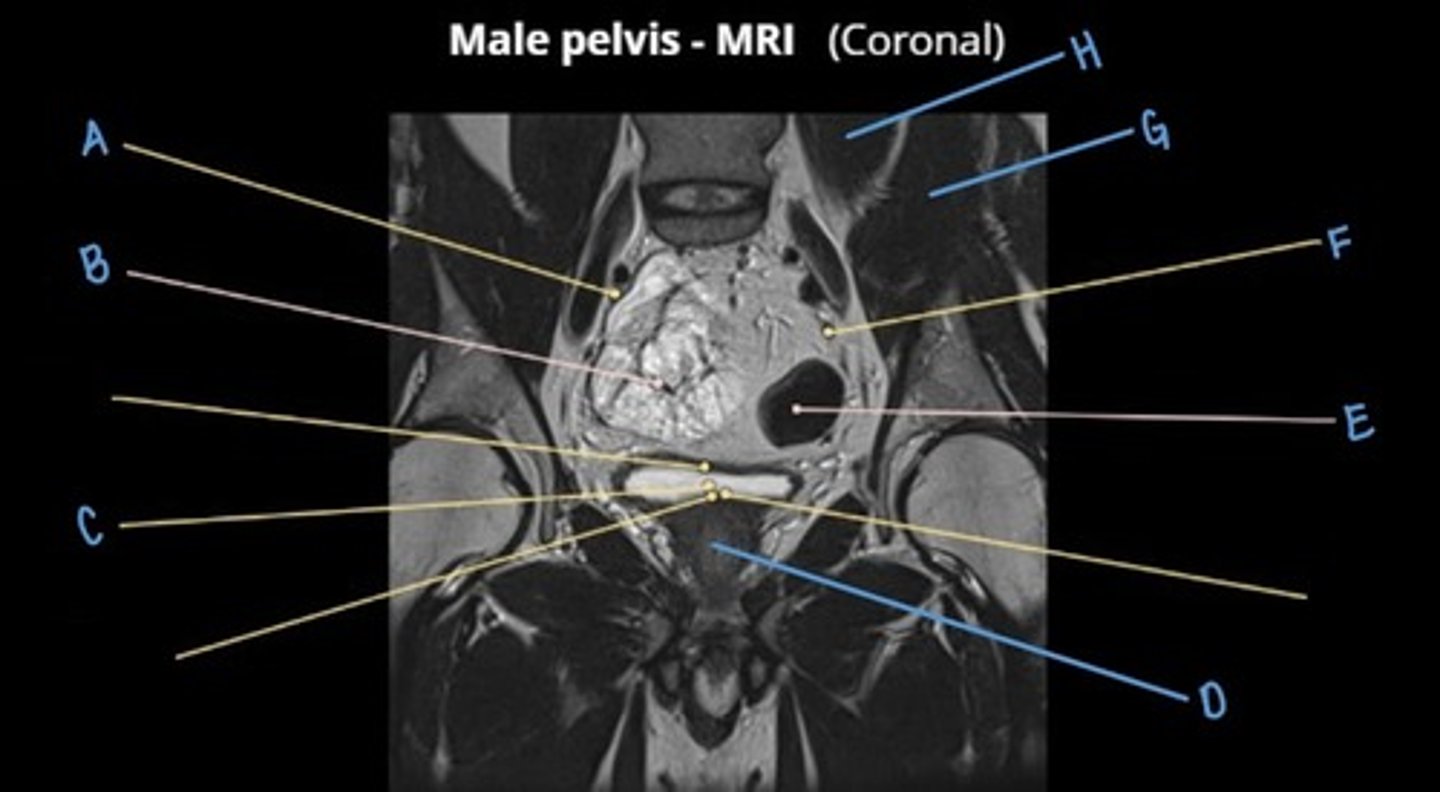

rectus abdominus muscle

A

bladder

B

prostate

C

obturator internus muscle

D

levator ani muscle (pubic diaphragm)

E

gluteus maximus muscle

F